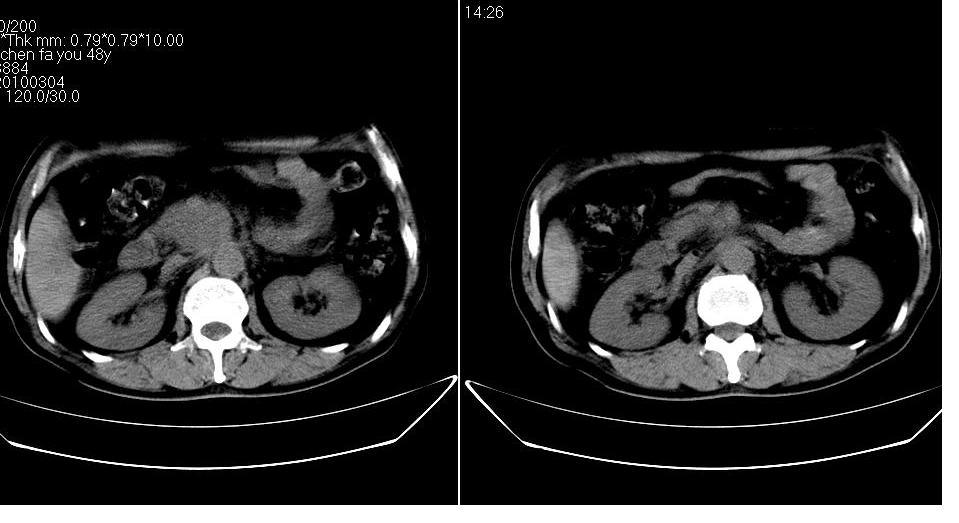

男 48岁,09年8月份在上级医院确诊胰头癌,准备在我院化疗。

胰头体积增大内见低密度影考虑为占位,肿瘤性病变可能性大。

胰头体积增大,外形不规则,密度欠均,支持胰头癌可能性大。